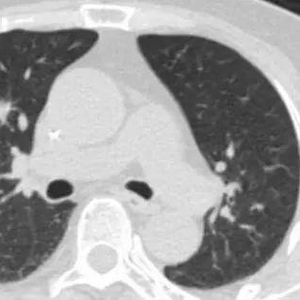

一年前,江阿姨复查体检时发现右肺上叶前段临近肺门有一孤立性结节,为边缘毛糙的实性结节,大小约为10×11毫米,医生考虑为原发或转移性肿瘤。家人赶紧带着江阿姨前往市区三甲医院就诊,辗转多家医院后,由于患者年纪大,加之合并症多,手术复杂且风险高,均未被收治。

近日,江阿姨再次到来到嘉定区中心医院血液内科治疗,得知江阿姨的诉求后,医院血液内科马上联系了胸外科李建新主任团队一同展开会诊。“结合患者CT考虑肺癌,且有手术指征。如果不限期手术,恐怕病情进展太快而失去最佳治愈机……”李建新表示。